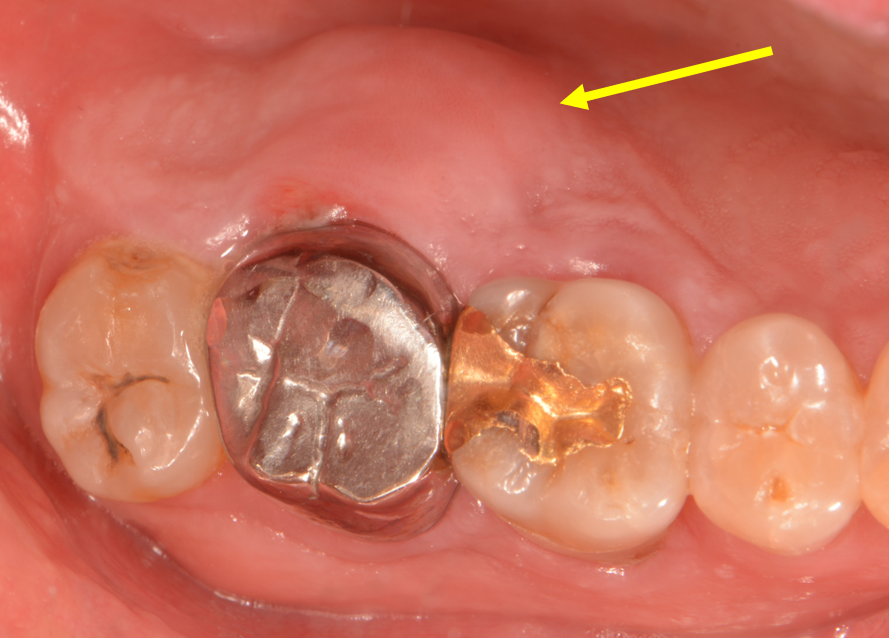

치주 농양 치료

Before

원래도 치조골이 소실되었거나 해서 잇몸 속으로 깊은 주머니(치주낭)가 있는 경우에

면역력이 떨어지거나 하면 크게 붓고 아픈 치주 농양이 생길 때가 있습니다.

이럴 때는 얼른 치과에 오셔서 잇몸치료 및 소독, 항생제 처치 등을 받으시면

조기에 통증 경감 및 증상 개선을 얻으실 수 있습니다.